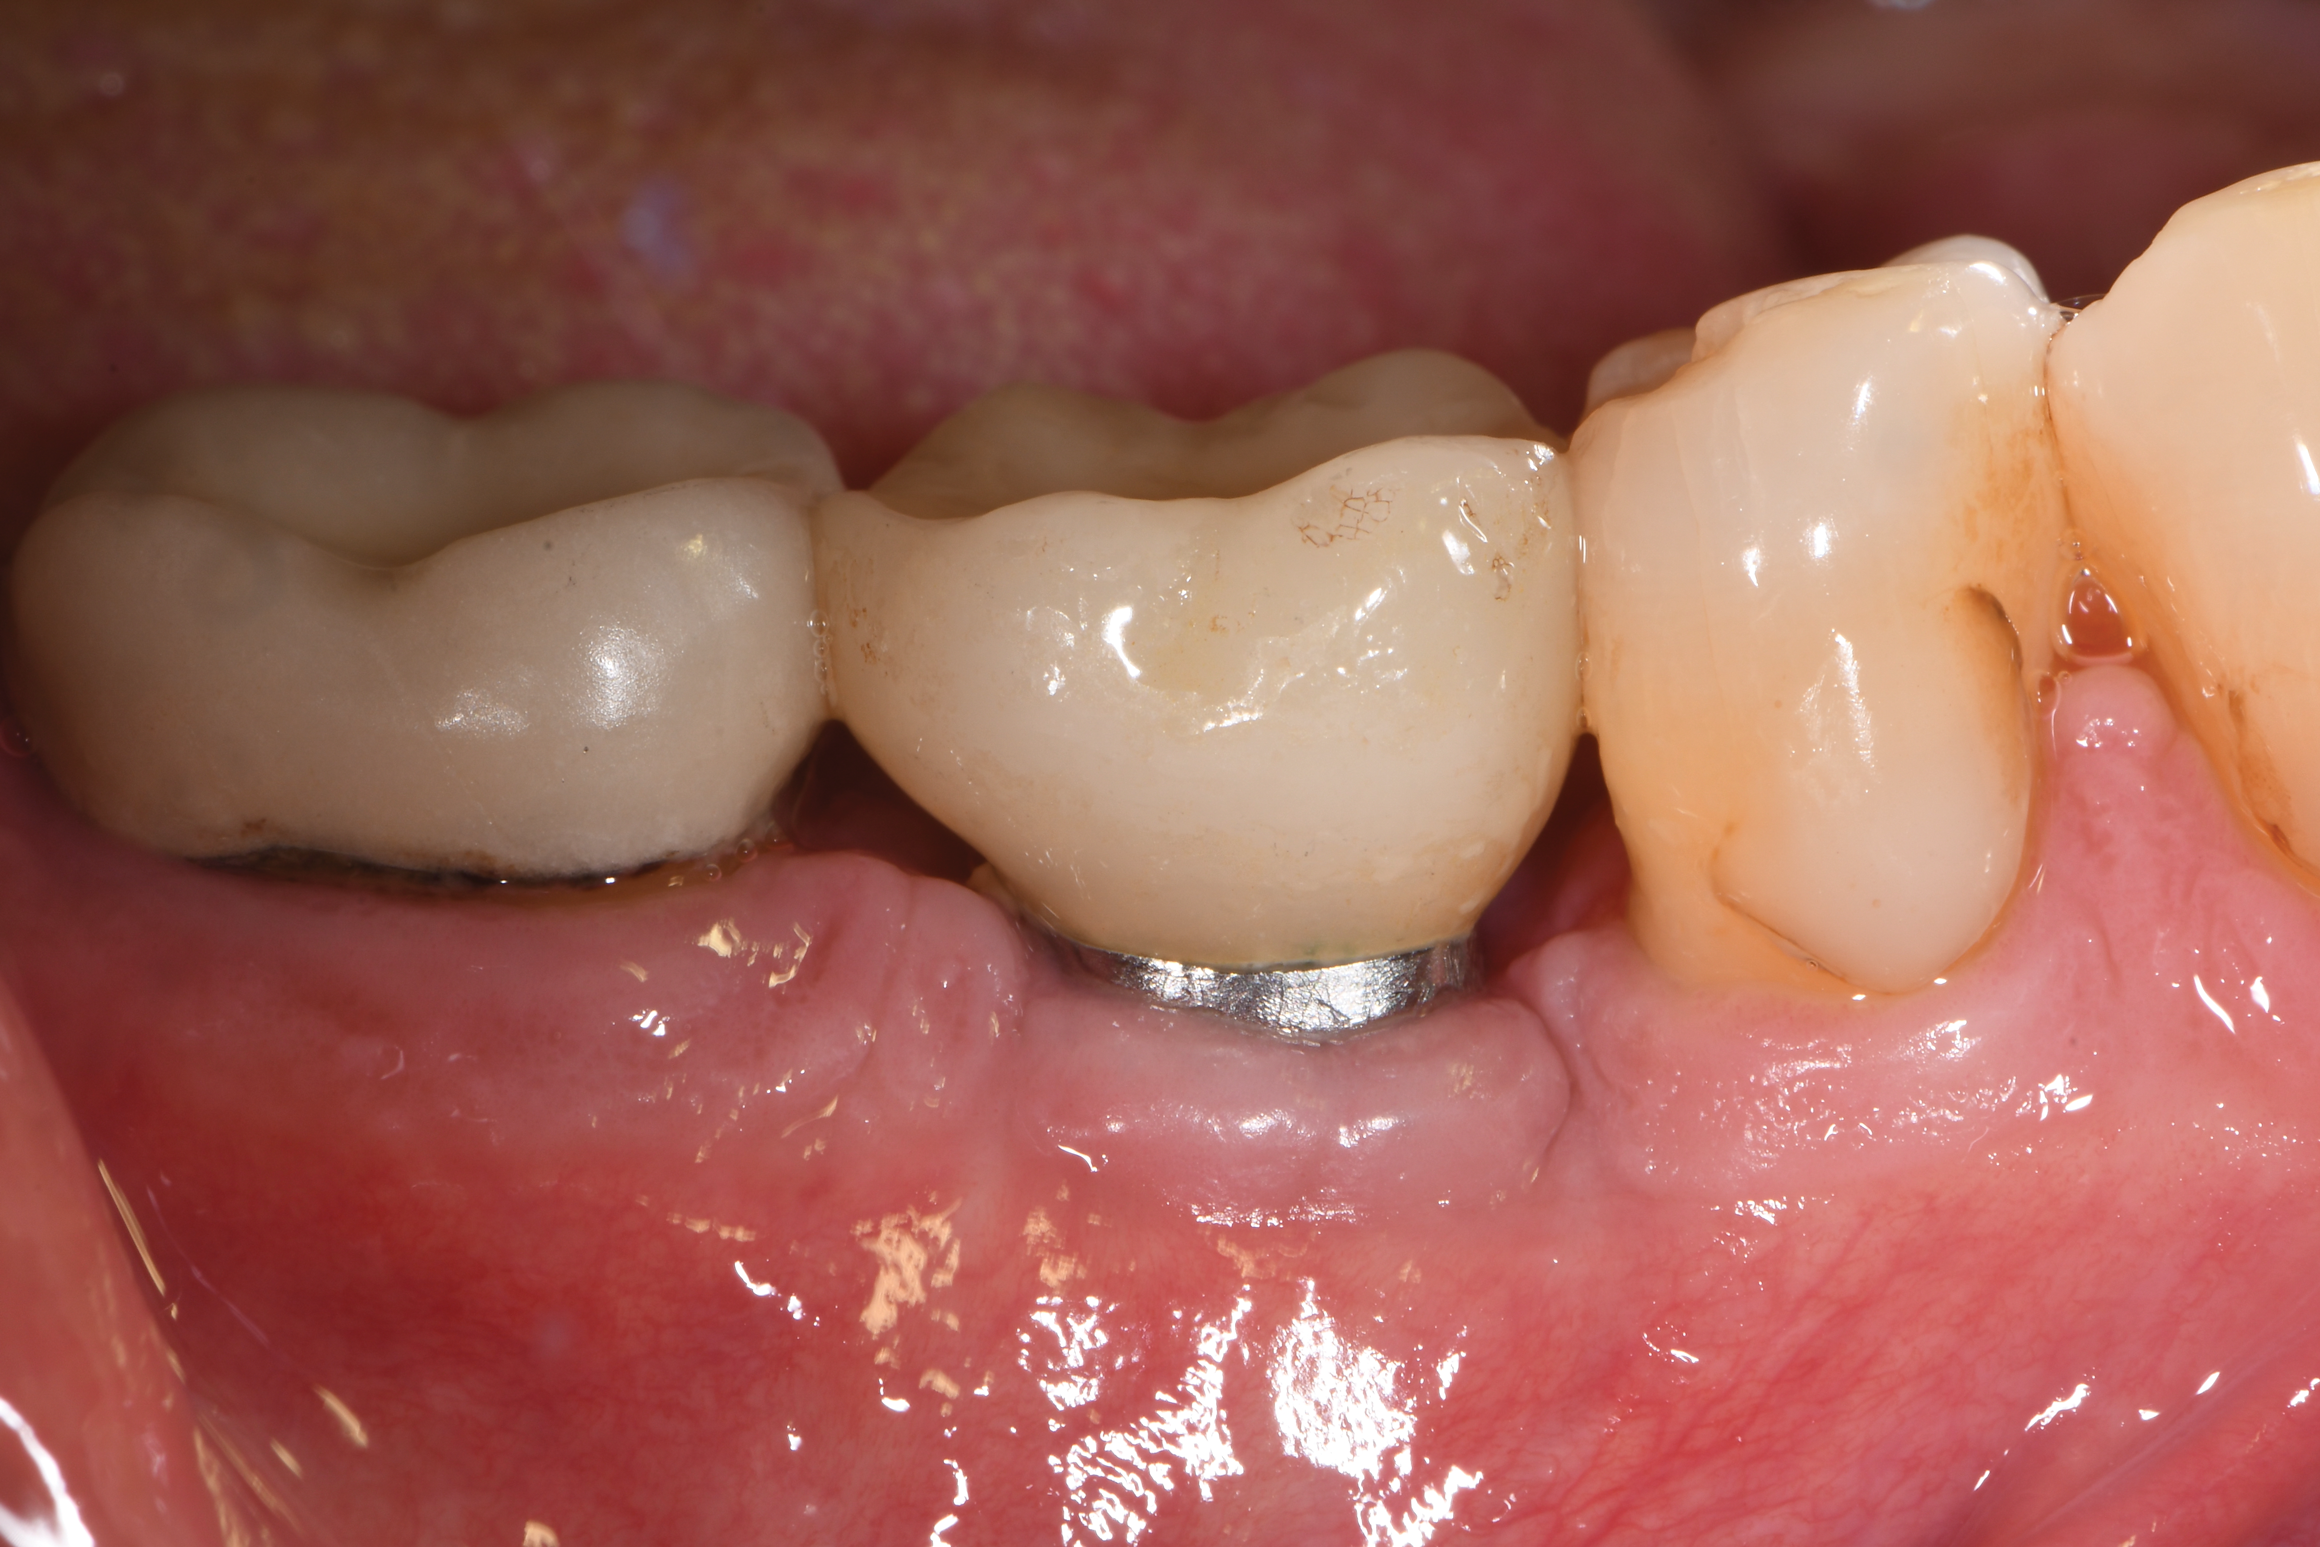

A 66-year-old man was referred for evaluation and treatment of a dental implant at the site of the mandibular right first molar, No. 30, which had been placed and restored 9 years prior. The patient's dentist had noted bone loss at the implant at the patient's recent semiannual maintenance visit. The patient's medical history included hypertension, for which losartan and amlodopine were being taken, and elevated cholesterol, for which rosuvastatin was being taken.

Based on clinical and radiographic examination of the area, the patient was diagnosed with moderate peri-implantitis subcategory A (Figure 10 and Figure 11).19 Pocket depths at this implant ranged up to 9 mm. A surgical approach was planned that included implantoplasty and guided bone regeneration.

Fig 10. Clinical presentation demonstrating purulent exudate from the dental implant along with inflammation of the gingival tissue.

Figure 10

Fig 11. Pretreatment radiograph demonstrating bone loss on the mandibular right first molar.

Figure 11